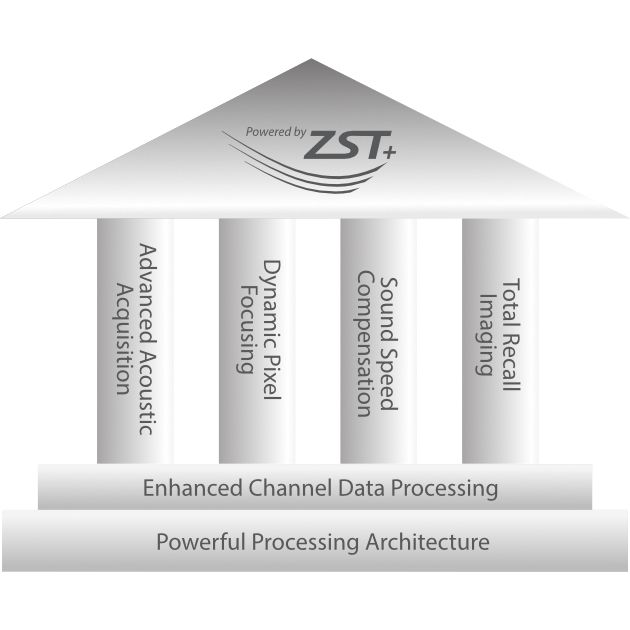

Point of Care, Reimagined

The TEX20 Series ultrasound system helps clinicians reimagine their clinical practice in demanding point-of-care environments like critical care, emergency medicine, and anaesthesia.